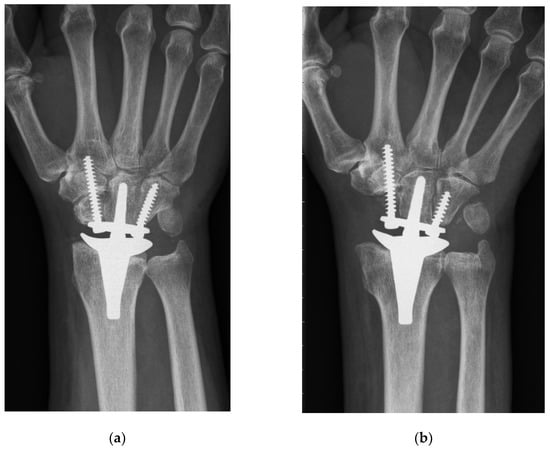

Both techniques implied a dorsal midline approach aligned with the third metacarpal. Next, the extensor retinaculum was divided obliquely over the third and fourth extensor compartment, and the joint capsule was opened by an open book incision. The CCR technique involved a manufacturer’s carpal cutting guide, which was aligned with the third metacarpal. Typically, the carpal resection included a resection of the lunate, triquetrum, proximal scaphoid, and the proximal cortex of the capitate, resulting in a cut perpendicular to the long axis of the radius (Figure 1a). On the contrary, the PRC method involved a sharp resection of the whole scaphoid, in addition to the prior mentioned bones, without using the carpal cutting guide. Moreover, the proximal part of the capitate and the tip of the hamate were resected using an oscillating saw, which was aligned perpendicularly to the long axis of the third metacarpal and strictly in the sagittal or dorsopalmar plane (Figure 1b).

To the best of our knowledge, PRC has never been previously described for primary TWA implantation in the current literature (see Table 5 for a summary of the literature). Gupta merely described, in his original surgical technique for ReMotion prosthesis, a salvage procedure for failed PRC or failed 4-corner fusions using TWA [1]. Interestingly, he recommended harvesting the pisiform for reconstruction of the missing distal pole of the scaphoid, where the radial screw is consecutively inserted. The present study shows that this additional step is not necessary, because fixation of the radial screw in the trapezoid and second metacarpal is sufficient for applying slight compression and rotational stability to the carpal prosthesis. Conney et al. [9] are the only authors who reported details on their carpal resection technique (i.e., the manufacturer’s recommended technique). Interestingly, we also found in the manufacturer’s operative technique that the producer recommends a more distal resection in patients with excessive carpal erosion or advanced degenerative joint disease [10]. However, we assume that this adaption would probably also not prevent TWA patients from being prone to suffering from radial impaction syndrome. This predominant clinical complication in the CCR group is most probably caused by the remaining distal pole of the scaphoid. Radiographically, this issue can be perfectly illustrated: Figure 2 shows a dorsopalmar radiograph of the wrist in neutral position with respect to radial and ulnar deviation (the third metacarpal and the long axis of the metacarpal are perfectly aligned). Even in this neutral position—without actively radially deviating the carpus—one can see contact or impingement between the prosthesis’s radial socket and the distal pole of the scaphoid. This situation led to four reoperations including resection of the distal pole of the scaphoid, which completely resolved the patient’s complaints. This further confirms the hypothesis of a correlation between the CCR technique and radial impaction syndrome. Moreover, we suppose that this complication is due to particular challenges associated with TWA. Inspecting the postoperative radiograph in Figure 1a, due to a sufficient distance between the socket and the scaphoid, the before-mentioned issue of radial impaction syndrome would be difficult to comprehend or predict. Despite intraoperative visual and fluoroscopic evaluation for any impingement in every extreme position while performing the CCR technique, radial impaction syndrome seems to develop in the postoperative course. One of the main reasons might be that TWA is very prone to periprosthetic, osseous remodeling. Osteophytes and osteolysis might cause or aggravate the morphologic correlate of radial impaction syndrome, which can be seen in Figure 2. This 6-year postoperative radiograph was taken from the same patient as in Figure 1a. The phenomenon has already been observed by Boeckstyns and Herzberg [11], who discuss possible reasons for osseous reactions in TWA. This publication mainly focused on radiolucency, which also represented a clinically asymptomatic, radiographic abnormality in both our cohorts.

Figure 1. Postoperative radiograph showing both applied implantation techniques: ReMotion implantation using (a) CCR (conventional carpal resection) and (b) PRC (proximal row carpectomy). The results merely differ in the distal pole of the scaphoid being removed in the PRC cohort.